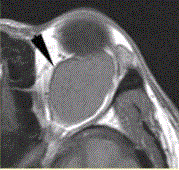

患者女,30岁,左眼球突出,运动障碍7个月。MRI平扫示左肌锥内等T信号影(下图)。增强扫描示均匀增强,眼肌、眼环正常。下述眼眶病变中,属于肌...

问题 患者女,30岁,左眼球突出,运动障碍7个月。MRI平扫示左肌锥内等T信号影(下图)。增强扫描示均匀增强,眼肌、眼环正常。 下述眼眶病变中,属于肌锥外病变的是

选项 A.海绵状血管瘤 B.炎性假瘤 C.泪腺瘤 D.淋巴管瘤 E.血管畸形 F.眼眶疏松结缔组织炎

答案 C